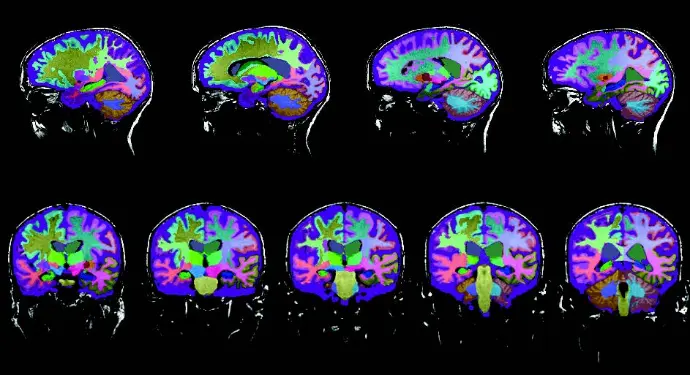

Report generation timing is essential for workload, workflow optimization and for prompt diagnosis in clinical settings. On average, US radiologists typically spend around 24 minutes reviewing a brain MRI and drafting a report [1,2]. That said, Neuroreader® reduces the time required to read an MRI from 24 minutes down to 10 minutes or less (by a cloud-based data analysis computer program). With advanced deep learning techniques, the computer program can visualize and quantify a large number of brain structures. Neuroreader® objectively analyzes DICOM images from MRI brain scans by comparing the patients brain volumes against a normative database with people of similar age, gender and head size. It measures and identifies atrophies of brain structures, such as the hippocampus, lateral ventricles, and brain lobes.

As accurate as the gold standard – manual vs automated segmentation

Often, when discussing controls of cognitive impairment and neurodegenerative diseases in general, the dissimilarity coefficients are very high, typically around 88%. This number typically holds across all types of cognitive decline. The reason why that is important is that if comparing the automated volumetric segmentation with Neuroreader® to the so-called gold standard anatomical segmentation by an expert anatomist, there is a high degree of agreement between the two methods. Except with volumetrics, you have a very high, thorough, and accurate segmentation in a short time-period, as hand drawn, manual segmentations typically take a lot longer. [7] This ultimately means that the speed of clinical decision-making is a lot faster when using an automated volumetric segmentation method like Neuroreader®, resulting in earlier diagnosis, adequate, and faster patient care.

Automated Segmentation

With automated volumetric data of brain MRI, you gain insights where the atrophy is occurring in the brain, which specific brain regions are affected, and which are not, as well as the magnitude to which they are affected. Furthermore, it gives us information about the progression. In comparison to manual hippocampal tracing, Neuroreader® can compute the volume of the hippocampus in less than five minutes and multiple structures of the entire brain in less than 10 minutes.